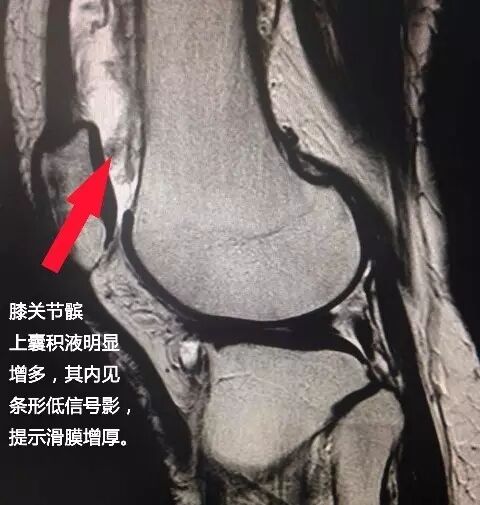

在众多检查方法中,核磁共振扫描(MRI)对滑膜病变的诊断最具优势性。滑膜病变引起的关节、滑囊积液,滑膜增厚及骨质侵蚀均能在MRI上清晰显示,另外MRI增强扫描还能对滑膜增生程度进行定量评价。MRI的强大诊断能力,会一次扫描发现关节疾病的诸多问题,这是一种直视化诊断,不用猜、不用推理;高场强的MRI完美图像,能将关节各部分结构清晰展示,而且扫描没有辐射、可复性强。

此为滑膜炎征象